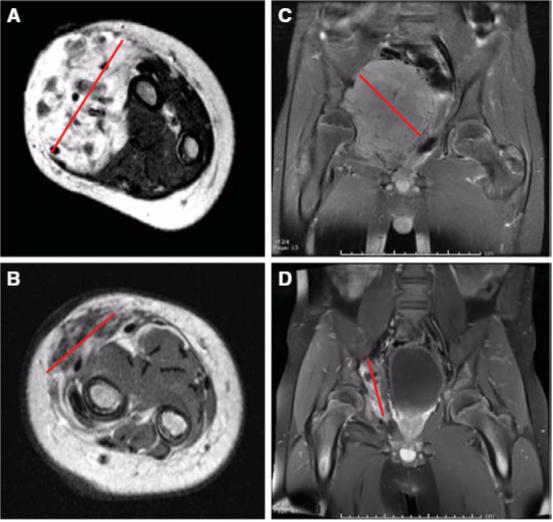

肺部多发肿瘤治疗后,肿瘤基本消失